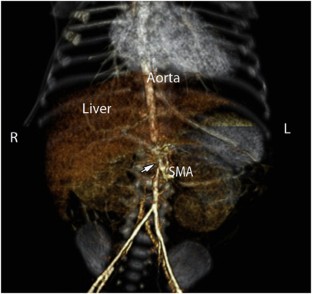

We report mid-aortic syndrome (MAC) in two preterm infants. Both infants developed malignant hypertension refractory to medical therapy and died early in infancy. Thus far, this account is of the two youngest patients with MAC.

Izraelit, A., Kim, M., Ratner, V. et al. Mid-aortic syndrome in two preterm infants. J Perinatol 32, 390–392 (2012). https://doi.org/10.1038/jp.2011.130